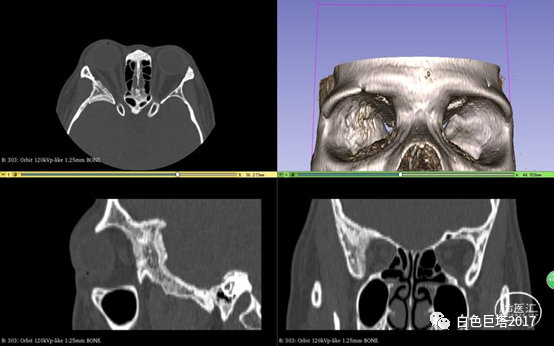

入院头颅CT检查提示右侧颞骨-眼眶后外侧壁骨质改变,眶内未见明显占位。报告考虑骨纤维异常增殖症可能性大。

3Dslicer重建可见眶后外侧壁骨质不均匀增厚,毛糙。